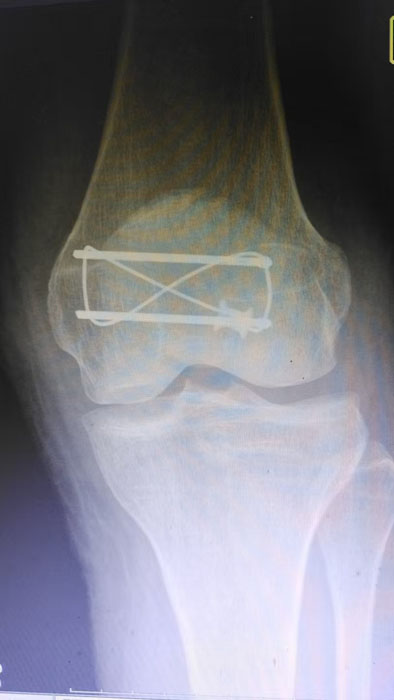

手术现场,徐三军主任凭借多年积累的临床经验和娴熟的手术技巧,精准完成骨折复位、钢板内固定、伤口缝合等一系列关键操作,动作规范流畅、精准高效,最大限度减少手术创伤。该院外科医护团队全程密切配合、协同发力,严格按照手术规范操作,全程严密监测患者心率、血压等生命体征,及时应对术中各类突发情况,全力保障手术安全。此次手术全程顺利,术中出血量少,患者生命体征始终平稳,术后患者顺利安返病房,为后续康复治疗奠定了坚实基础。

此次手术不仅是一次成功的临床救治实践,更是一堂生动鲜活的“实战教学课”。手术过程中,徐三军结合自身临床经验,同步向该院外科医护人员讲解髌骨骨折手术的操作要点、规范流程、风险防控技巧及术后康复核心要点,采取“手把手”带教、点对点指导的方式,耐心解答医护人员提出的疑问,帮助基层医护人员理清诊疗思路、提升操作能力。此次带教有效提升了卫生院外科团队在骨科手术及围手术期管理方面的专业水平,为基层医疗服务能力持续提升注入了强劲动力。